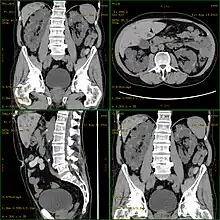

| Severely affected polycystic kidneys removed at time of transplantation | |

| Diagnostic method | MRI, CT scan, Ultrasound[1] |

Diagnosis may be suspected from one, some, or all of the following: new onset flank pain or red urine; a positive family history; palpation of enlarged kidneys on physical exam; an incidental finding on abdominal sonogram; or an incidental finding of abnormal kidney function on routine lab work (BUN, serum creatinine, or eGFR). Definitive diagnosis is made by abdominal CT exam.

Polycystic kidney disease can be ascertained via a CT scan of abdomen, as well as, an MRI and ultrasound of the same area.[23] A physical exam/test can reveal enlarged liver, heart murmurs and elevated blood pressure[1]